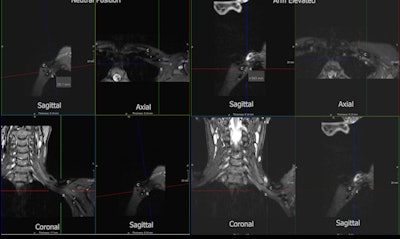

At the Princess Alexandra Hospital, imaging is performed on a 3-tesla scanner with sequences consisting of 3D SPACE [sampling perfection with application-optimized contrasts using a different flip angle evolution] STIR [short tau inversion recovery] images in a coronal plane orientated to the neurovascular bundle, sagittal Dixon T2 images, and T-weighted images with the imaged volume extending through the supraclavicular fossa to the humerus.

Sequences are performed with the arm in both neutral position and in abduction with external rotation. Additionally, a sagittal T2 cervical spine is performed to assess cervical nerve roots.